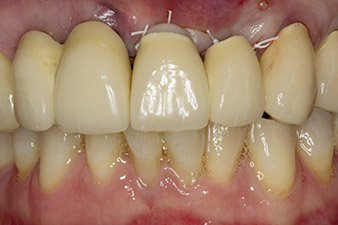

initial radiological findings

Fig. 1: The initial radiological findings revealed a splinted crown restoration requiring replacement. When the restoration was removed, teeth 21 and 22 were unintentionally extracted along with it.

When the patient first presented, teeth 21, 22 and 23 had been restored with splinted crowns, now 19 years old, which were bonded to the implants at positions 12/11 by an attachment (cf. Fig. 2).

The x-ray revealed horizontal bone loss around teeth 21 and 22 (Fig. 1). When the crown block was removed, these teeth were unintentionally extracted with it.